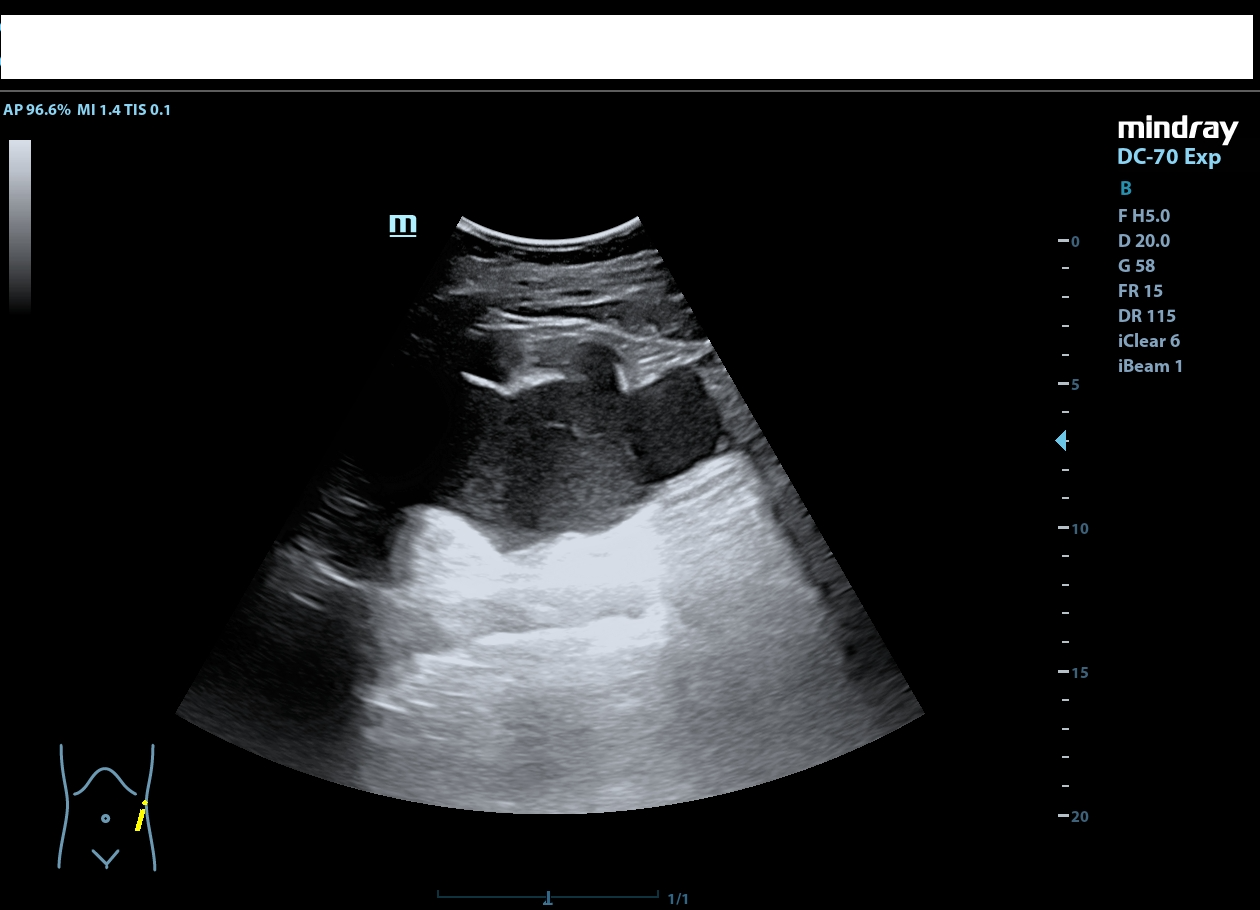

Riñón derecho de ecoestructura conservada, con dilatación pielocalicial grado I. Riñón izquierdo con adelgazamiento cortical y ureterohidronefrosis grado IV, sin poder localizarse el origen de la obstrucción, ausencia de jet ureteral izquierdo. Hallazgos sugestivos de síndrome de la unión pieloureteral.